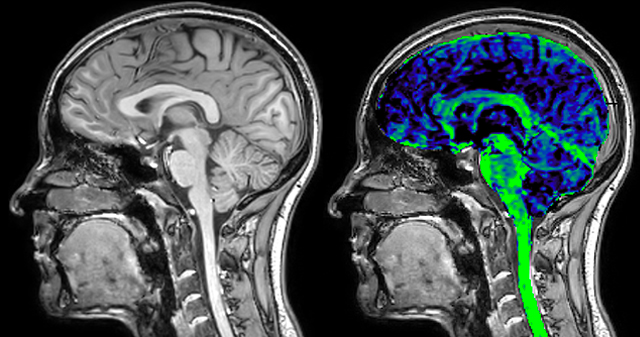

T1 - Weighted, Myelin Water Fraction Superimposed

Spinal cord coverage

Smaller, more isotropic voxels

Excellent detail in quantitative maps

Images courtesy of Adam Dvorak, Department of Physics and Astronomy, University of British Columbia

Dr. Rauscher says, “With better gradients we can use a shorter echo spacing on the spin echo, so we get better sampling of the rapidly decaying myelin signal, which typically has T2 of around 10-20 milliseconds at 3 Tesla. If we can reduce echo spacing from about 8 to 5-6 milliseconds, we get a much better sampling of the short decay component and increase our SNR, which is a big advantage. The same is true for multi-echo gradient echo which we use for susceptibility mapping and for mapping venous vessels in MS.”

QSM based on a Compressed SENSE multi-echo SWI.